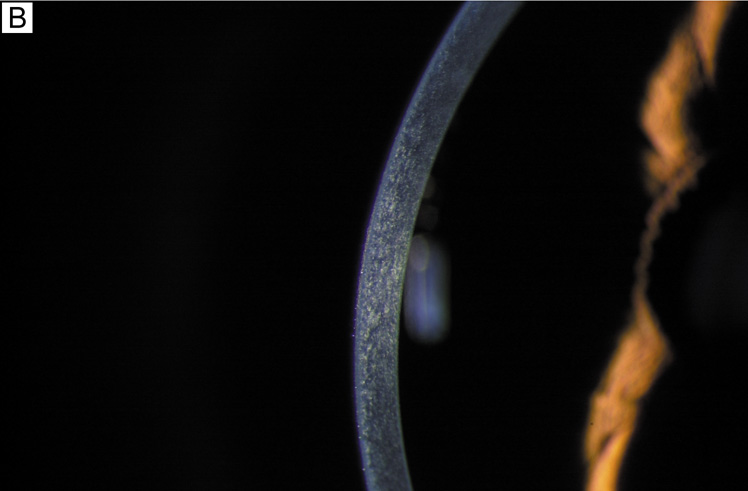

A number of factors have been known to acutely affect the barrier function of the endothelium, including the following: reversible disruption of cell junctions (calcium-free solutions or glutathione-restricted solutions [Fig. 25]), mechanical damage (e.g., trauma, intraocular lens [IOL] insertion, surgical instruments), or chemical injury (e.g., noncomplete toxic intraocular solutions, preservatives). Fortunately, if enough of the remaining viable cells are able to migrate, recover the posterior corneal surface by spreading out over a larger surface area, and reestablish the intercellular cell junctions, the barrier function of the corneal endothelium is restored.

Fig. 25. Scanning electron micrograph (1,000×) of the endothelium after perfusion with calcium free irrigating solutions after 30 minutes. Without calcium, endothelial cells round up into small mounds as the intercellular junctions become disrupted, resulting in exposure of large areas of Descemet's membrane, loss of barrier function, and corneal swelling. E, endothelial cells; ES, extracellular space. Bar = 10 μm.